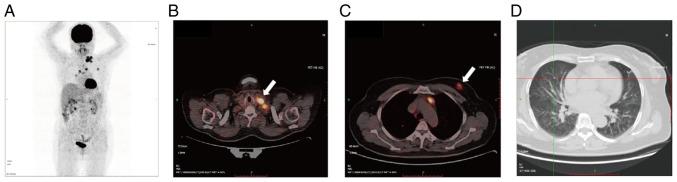

Multiple primary cancers (MPCs) have an increasing incidence rate due to the detection of early stages of cancer and the development of effective therapeutic strategies. MPCs are less common compared with metachronous cancers. Therefore, distinguishing synchronous primary tumors from metastasis and developing an individualized treatment strategy can be challenging. In the present study, the case of a 70-year-old female who was referred to The First Hospital of Jilin University (Changchun, China) with an enlarged left cervical lymph node and no other clinical manifestations is reported. Radiography revealed distinct lesions in the left breast, left cervical lymph node and bilateral lungs. Subsequently, a biopsy was performed in all three lesions and then each specimen was subjected to immunohistochemistry, fluorescence hybridization, amplification refractory mutation system-PCR and next-generation sequencing (NGS). Disease-related enrichment of lymph node mutant genes and Gene Ontology Biological Process enrichment of breast, as well as lung, mutant genes were performed using the Database for Annotation, Visualization and Integrated Discovery. Based on the molecular assessment, the patient was finally diagnosed with breast invasive ductal carcinoma, primary lung adenocarcinoma and cervical lymph node metastatic lung adenocarcinoma. Since primary synchronous breast and lung cancer (SBLC) is rare, a molecular assessment, particularly using NGS, could provide important information for both the diagnosis and treatment of SBLC.

由于癌症早期检测技术的发展以及有效治疗策略的出现,多原发性癌(MPCs)的发病率呈上升趋势。与异时性癌相比,MPCs较为少见。因此,区分同步原发性肿瘤与转移瘤并制定个体化治疗策略具有挑战性。在本研究中,报告了一名70岁女性的病例,该患者因左颈部淋巴结肿大被转诊至吉林大学第一医院(中国长春),无其他临床表现。影像学检查显示左乳、左颈部淋巴结及双肺有明显病变。随后,对所有三个病变进行了活检,然后对每个标本进行了免疫组织化学、荧光杂交、扩增阻滞突变系统聚合酶链反应(ARMS-PCR)和二代测序(NGS)。使用注释、可视化和综合发现数据库(DAVID)对淋巴结突变基因的疾病相关富集以及乳腺和肺突变基因的基因本体生物学过程富集进行了分析。基于分子评估,该患者最终被诊断为乳腺浸润性导管癌、原发性肺腺癌和颈部淋巴结转移性肺腺癌。由于原发性同步性乳腺癌和肺癌(SBLC)较为罕见,分子评估,特别是使用NGS,可为SBLC的诊断和治疗提供重要信息。